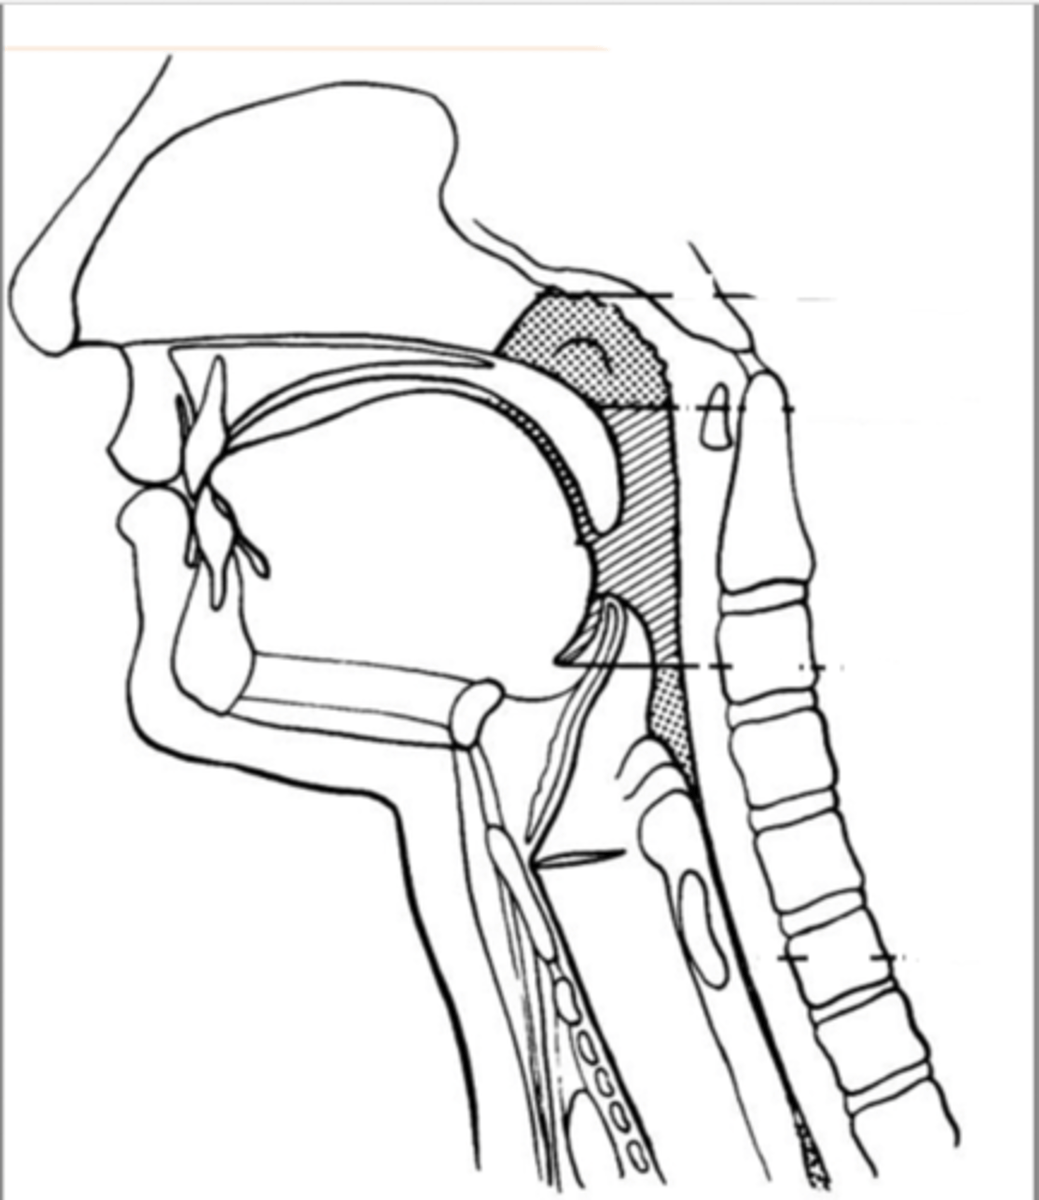

Label Nasopharynx (lateral view)

Label Nasal cavity (lateral view)

Label oropharynx (lateral view)

Label hypopharynx/ hylolarynx

Label tongue (lateral view)

Label soft velum/ palate (lateral view)

Label hard palate (lateral view)

Label mandible (lateral view)

Label base of tongue (lateral view)

label hyoid bone (lateral view)

Label epiglottis (lateral view)

label Line of true vocal folds (lateral view)

label Thyroid cartilage (anteriorly) (lateral view)

Label posterior cricoid (lateral view)

Label esophagus (lateral view)